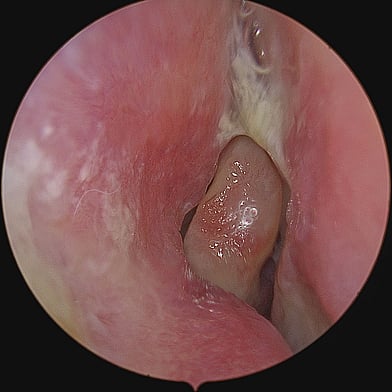

On the other hand, Chronic Sinusitis / Rhinosinusitis (CRS) is an inflammation and swelling of the sinus lining lasting longer than 12 weeks, often associated with persistent symptoms despite treatment. It can be caused by infections (bacterial / viral / fungal), allergies, environmental irritants like pollutants, anatomical abnormalities (e.g. nasal polyps) or autoimmunological factors. Patients with CRS display symptoms associated with the acute type along with headaches, a diminished sense or loss of smell (Hyposmia or Anosmia), or post-nasal drip.

Diagnosing chronic rhinosinusitis involves a comprehensive evaluation, which may include medical history and physical examination, nasal endoscopy, imaging studies, allergy testing, and conducting nasal and sinus cultures.